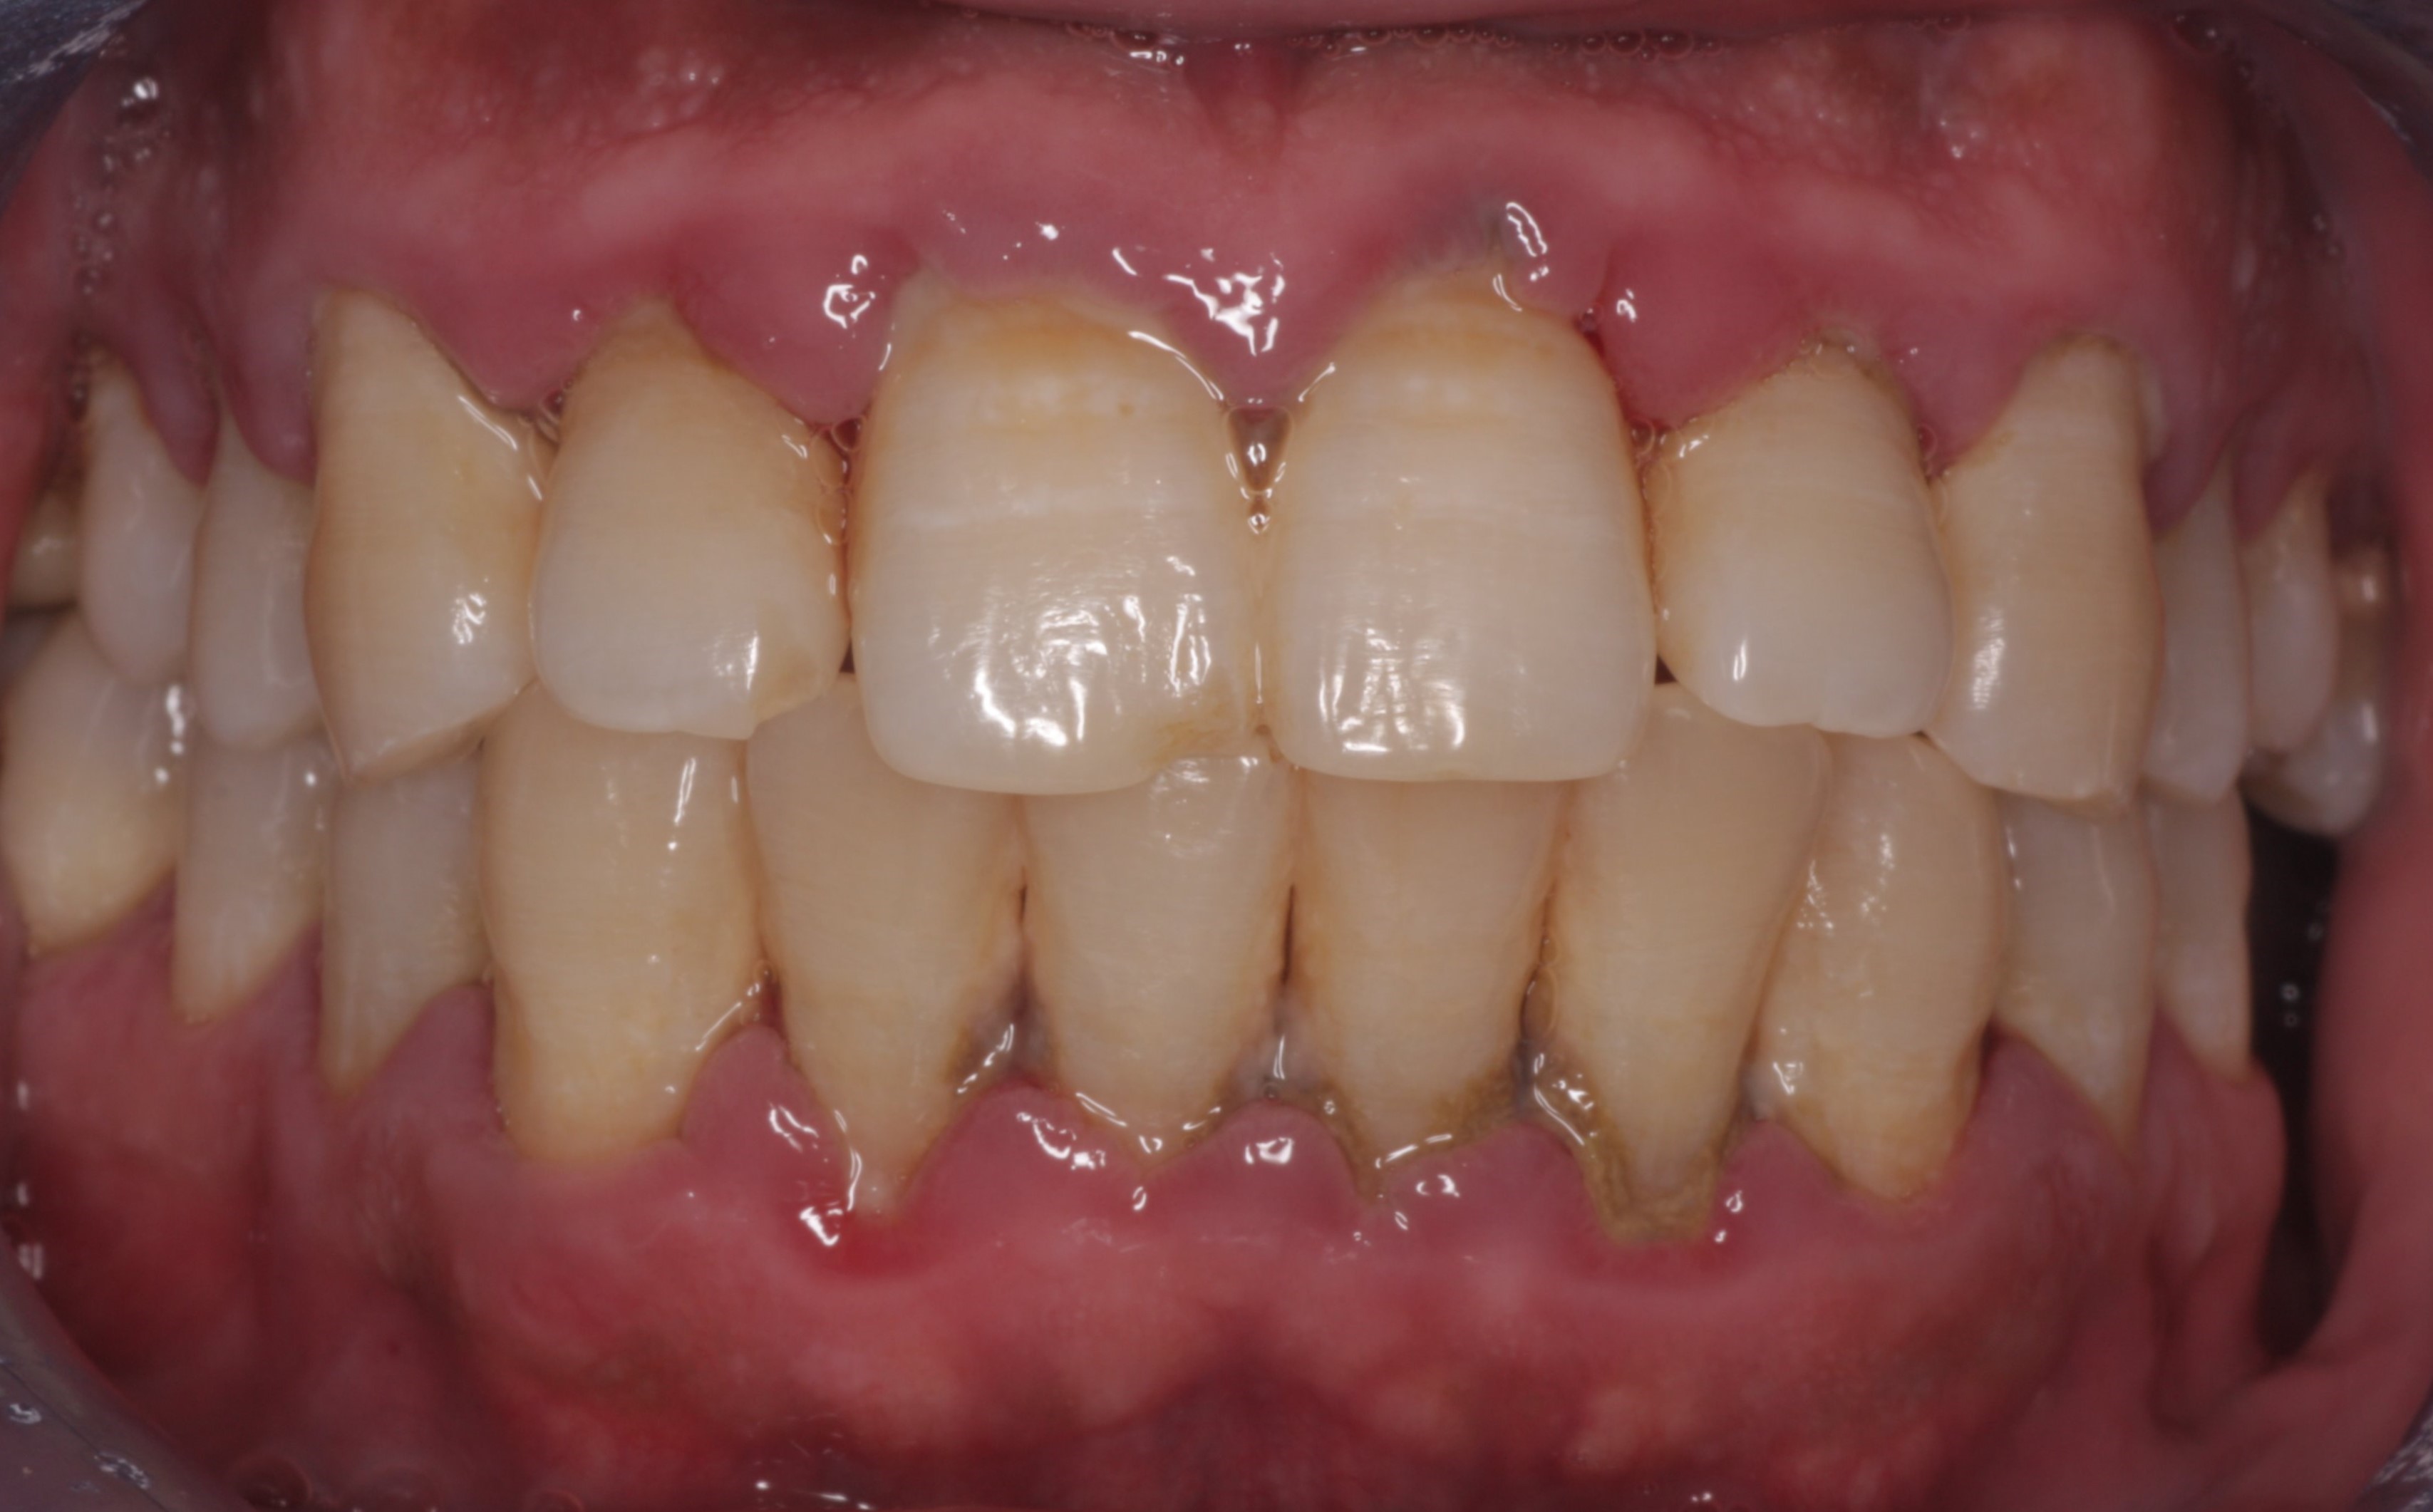

Periodontitis

The clinical presentation and diagnostic criteria that indicate a diagnosis of periodontitis are:

Clinical presentation:

- Patient may have red, swollen and inflamed marginal gingival tissue.

- Patient may have halitosis and calculus deposits, both supra- and subgingivally.

- Patient may have drifting or mobile teeth.

- Periodontal pocketing.

- Bleeding on probing.

- Visible interdental recession may be present.

- Bone loss from the CEJ observed on radiographs.

Diagnostic criteria:

- Attachment loss >4 mm at more than 2 non-adjacent sites.

- Bone levels on radiographs >2 mm apically from CEJ.